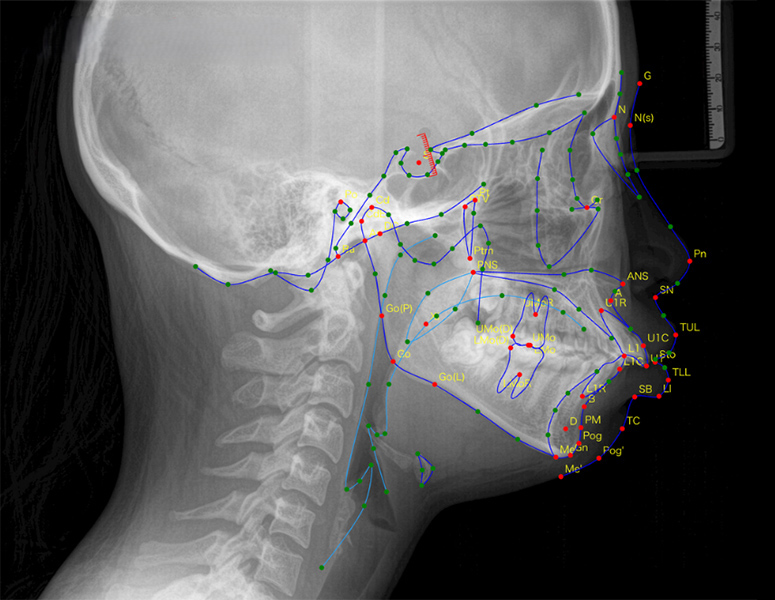

DIP Magic Trace™

業界最多クラス159測定点を

数秒で自動計測

セファログラムをアップロードするだけで、AIが顔貌・骨格・咬合・軟組織・気道まで、159測定点をわずか数秒で自動トレース。従来30分以上必要だった作業を劇的に効率化します。 また専門医レベルの精度で、経験や習熟度に左右されない標準化が可能です。 手動修正にも対応し、効率と精度の両立を実現します。 DIP Magic Compare™